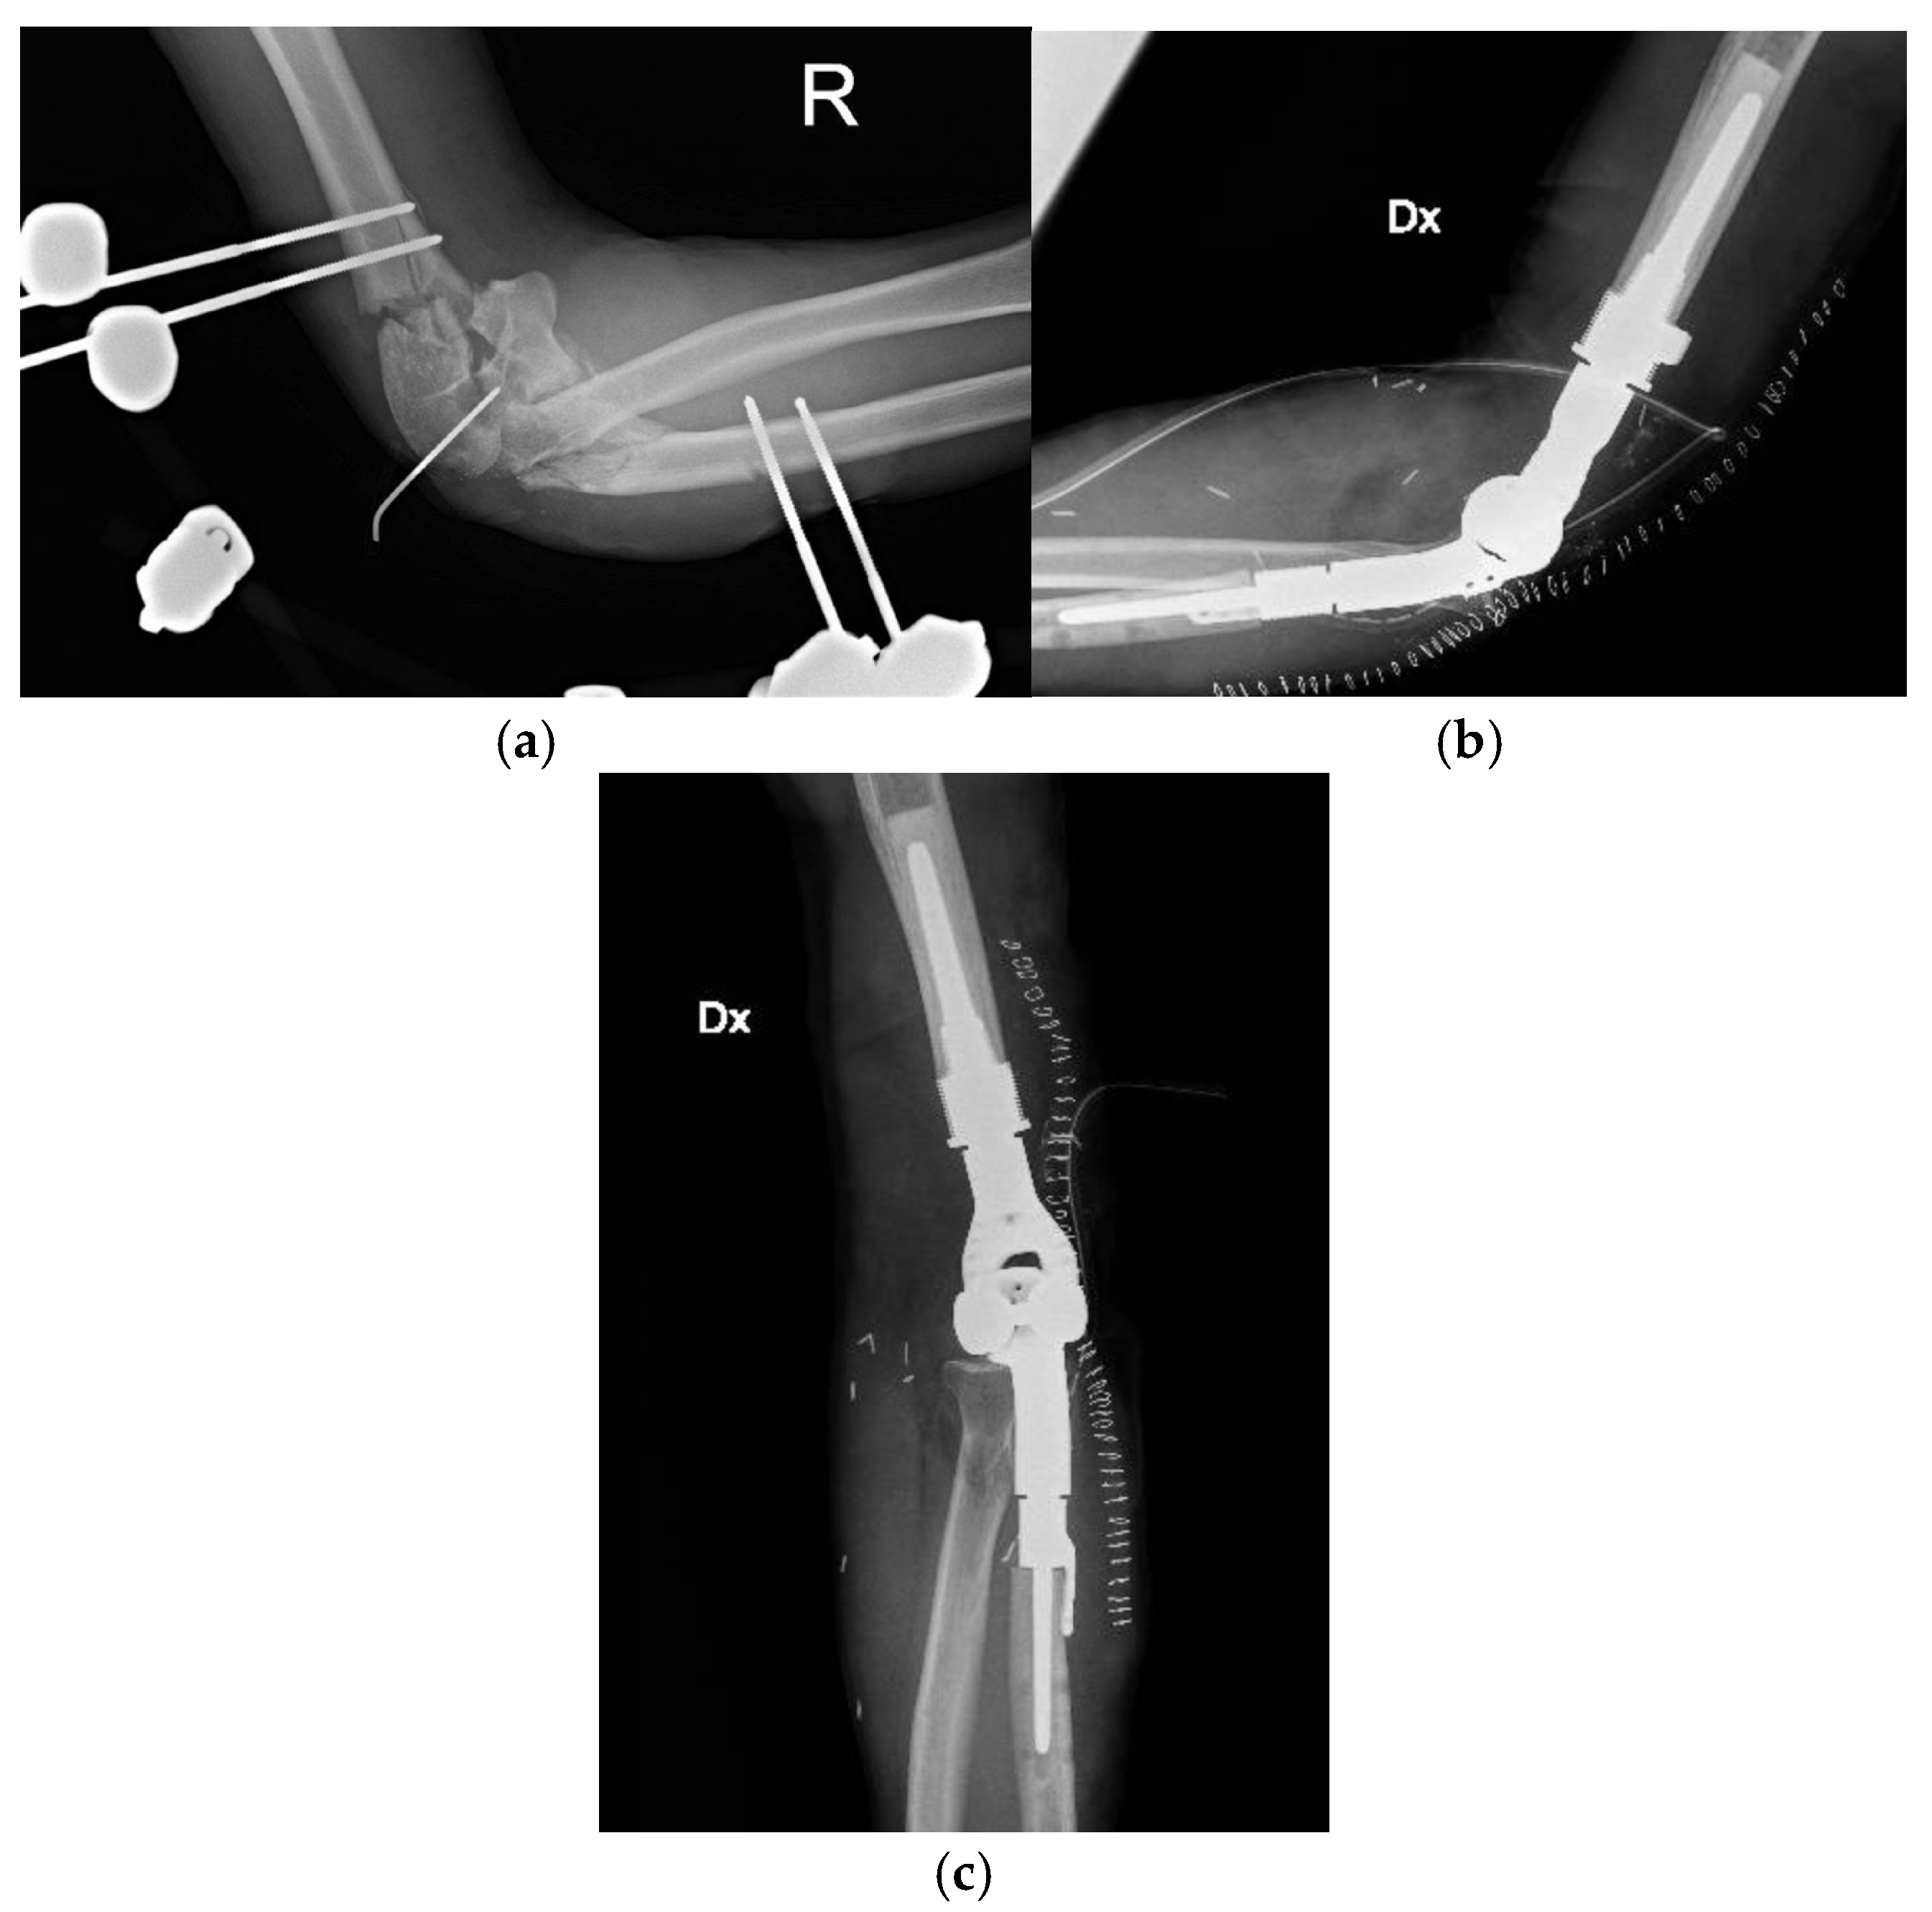

4.2. Case 2: Complex Open Fracture of the Elbow